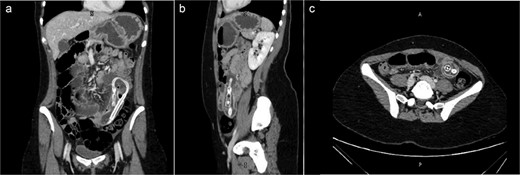

Following the initial evaluations, the patient had an urgent computed tomography (CT) abdominal scan, which revealed that the migrating collapsed gastric balloon, which was trapped in the small bowel loops with proximally dilated loops, was the cause of the small intestinal obstruction (SBO) (Fig. 2). The migrating IGB was determined to be the source of the patient's small intestinal blockage. As the patient was hemodynamically stable and the goal was for the balloon to transit naturally down the alimentary tract, the surgical team advised conservative care at this point.

(a) Coronal view (b) sagittal view (c) axial view of the abdominal CT scan with oral water-soluble contrast showing IGB migrated and impacted in the jejunum with the proximal SBO.